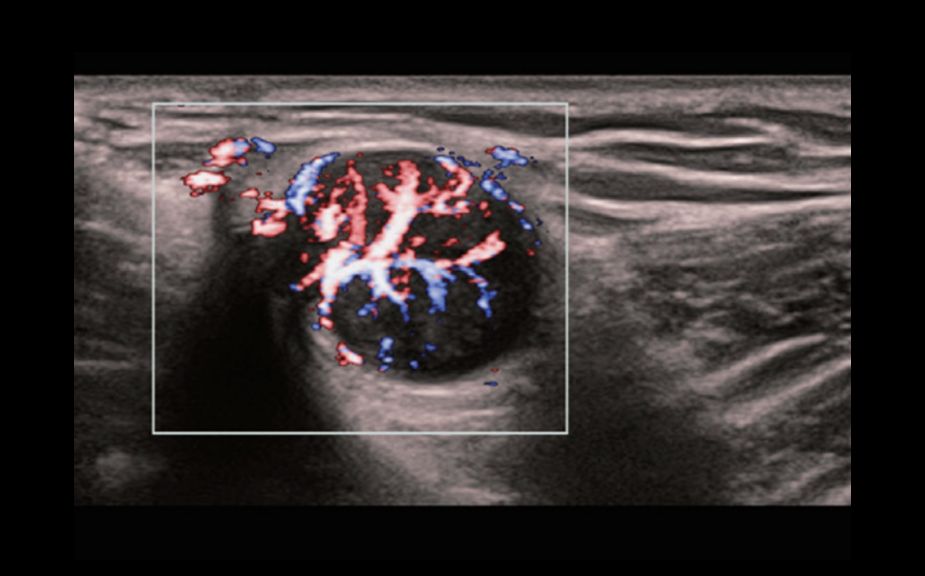

–ù–Ψ–≤–Β–Ι―à–Η–Ι –Ω–Ψ–¥―Ö–Ψ–¥ –Κ –Η–Ζ―É―΅–Β–Ϋ–Η―é ―¹–Ψ―¹―É–¥–Η―¹―²–Ψ–Ι –≥–Β–Φ–Ψ–¥–Η–Ϋ–Α–Φ–Η–Κ–Η: V Flow

–‰―¹–Ω–Ψ–Μ―¨–Ζ―É―é―²―¹―è –Φ–Α―Ä–Κ–Η―Ä–Ψ–≤–Α–Ϋ–Ϋ―΄–Β ―Ü–≤–Β―²–Ψ–Φ –≤–Β–Κ―²–Ψ―Ä–Α –¥–Μ―è –Η–Ϋ–¥–Η–Κ–Α―Ü–Η–Η –Ζ–Ϋ–Α―΅–Β–Ϋ–Η―è ―¹–Κ–Ψ―Ä–Ψ―¹―²–Η –Η –Ϋ–Α–Ω―Ä–Α–≤–Μ–Β–Ϋ–Η―è –¥–≤–Η–Ε–Β–Ϋ–Η―è –Κ–Μ–Β―²–Ψ–Κ –Κ―Ä–Ψ–≤–Η. –ë–Μ–Α–≥–Ψ–¥–Α―Ä―è ―¹–≤–Β―Ä―Ö–≤―΄―¹–Ψ–Κ–Ψ–Ι ―΅–Α―¹―²–Ψ―²–Β –Κ–Α–¥―Ä–Ψ–≤ V Flow –Ψ–±–Β―¹–Ω–Β―΅–Η–≤–Α–Β―² ―΅―Ä–Β–Ζ–≤―΄―΅–Α–Ι–Ϋ–Ψ ―΅–Β―²–Κ―É―é, ―²–Ψ―΅–Ϋ―É―é –Η –Ϋ–Β–Ζ–Α–≤–Η―¹–Η–Φ―É―é –Ψ―² ―É–≥–Μ–Α –Κ–Ψ–Φ–Ω–Μ–Β–Κ―¹–Ϋ―É―é –Ψ―Ü–Β–Ϋ–Κ―É ―¹–Ψ―¹―É–¥–Η―¹―²–Ψ–Ι –≥–Β–Φ–Ψ–¥–Η–Ϋ–Α–Φ–Η–Κ–Η ―¹ –≤–Ψ–Ζ–Φ–Ψ–Ε–Ϋ–Ψ―¹―²―¨―é –≤―¹–Β―¹―²–Ψ―Ä–Ψ–Ϋ–Ϋ–Β–≥–Ψ –Α–Ϋ–Α–Μ–Η–Ζ–Α.

V Flow

–ù–Ψ–≤–Β–Ι―à–Η–Ι –Ω–Ψ–¥―Ö–Ψ–¥ –Κ –Η–Ζ―É―΅–Β–Ϋ–Η―é ―¹–Ψ―¹―É–¥–Η―¹―²–Ψ–Ι –≥–Β–Φ–Ψ–¥–Η–Ϋ–Α–Φ–Η–Κ–Η: V Flow

–‰―¹–Ω–Ψ–Μ―¨–Ζ―É―é―²―¹―è –Φ–Α―Ä–Κ–Η―Ä–Ψ–≤–Α–Ϋ–Ϋ―΄–Β ―Ü–≤–Β―²–Ψ–Φ –≤–Β–Κ―²–Ψ―Ä–Α –¥–Μ―è –Η–Ϋ–¥–Η–Κ–Α―Ü–Η–Η –Ζ–Ϋ–Α―΅–Β–Ϋ–Η―è ―¹–Κ–Ψ―Ä–Ψ―¹―²–Η –Η –Ϋ–Α–Ω―Ä–Α–≤–Μ–Β–Ϋ–Η―è –¥–≤–Η–Ε–Β–Ϋ–Η―è –Κ–Μ–Β―²–Ψ–Κ –Κ―Ä–Ψ–≤–Η. –ë–Μ–Α–≥–Ψ–¥–Α―Ä―è ―¹–≤–Β―Ä―Ö–≤―΄―¹–Ψ–Κ–Ψ–Ι ―΅–Α―¹―²–Ψ―²–Β –Κ–Α–¥―Ä–Ψ–≤ V Flow –Ψ–±–Β―¹–Ω–Β―΅–Η–≤–Α–Β―² ―΅―Ä–Β–Ζ–≤―΄―΅–Α–Ι–Ϋ–Ψ ―΅–Β―²–Κ―É―é, ―²–Ψ―΅–Ϋ―É―é –Η –Ϋ–Β–Ζ–Α–≤–Η―¹–Η–Φ―É―é –Ψ―² ―É–≥–Μ–Α –Κ–Ψ–Φ–Ω–Μ–Β–Κ―¹–Ϋ―É―é –Ψ―Ü–Β–Ϋ–Κ―É ―¹–Ψ―¹―É–¥–Η―¹―²–Ψ–Ι –≥–Β–Φ–Ψ–¥–Η–Ϋ–Α–Φ–Η–Κ–Η ―¹ –≤–Ψ–Ζ–Φ–Ψ–Ε–Ϋ–Ψ―¹―²―¨―é –≤―¹–Β―¹―²–Ψ―Ä–Ψ–Ϋ–Ϋ–Β–≥–Ψ –Α–Ϋ–Α–Μ–Η–Ζ–Α.

V Flow